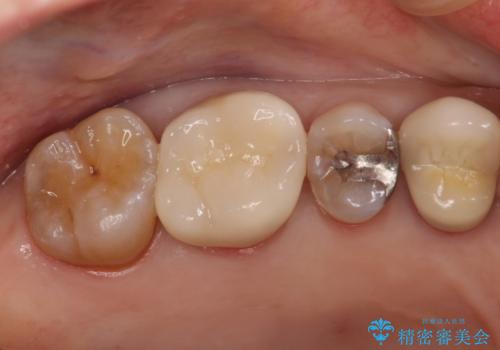

セラミッククラウンによるむし歯治療

- 他院で入れたセラミックインレーがかけたことを主訴に来院されました。

他の部位にもむし歯を認めたため、優先度の高い歯から治療を行っております。

咬合力が強くかかる部分には欠けるリスクのほとんどない金属を用いることが最良ですが審美性に劣ります。

今回は白い材料での修復を希望されたため、欠けるリスクが高いセラミックインレーは避け、セラミッククラウンにて治療を行いました。